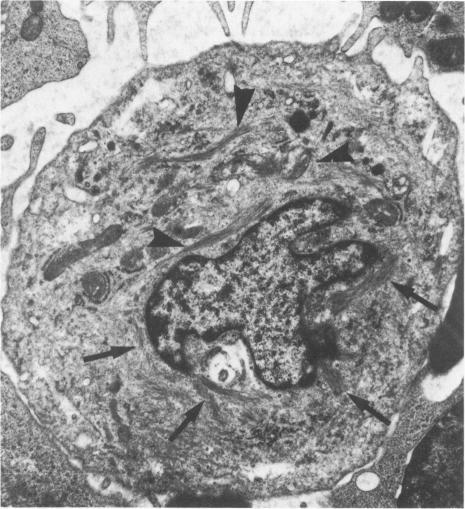

An immunoperoxidase technique employing antibody to prekeratin was used to study distribution and pattern of staining of prekeratin filaments in cytological smears obtained from 42 specimens of pleural and peritoneal effusions (27 benign, 15 malignant). The smears were either air-dried or ethanol-fixed. Both benign and malignant mesothelial cells showed distinctive peripheral or perinuclear staining patterns which differed from the characteristic arborizing pattern in adenocarcinoma cells. The ultrastructure of these 2 cell types studied in 27 body fluids (12 benign, 15 malignant) and in 13 malignant tumors (3 mesotheliomas, 10 adenocarcinomas) showed a distinctive localizaton of intermediate filaments which corresponded to and could explain the pattern of staining obtained using the immunoperoxidase technique. The immunohistochemical and ultrastructural findings appeared characteristic for benign and malignant mesothelial cells as well as for adenocarcinoma cells, and could be used as markers to differentiate mesothelial tumors and reactive mesothelial cells from adenocarcinomas.

采用抗前角蛋白抗体的免疫过氧化物酶技术,研究了取自42例胸腔和腹腔积液标本(27例良性,15例恶性)的细胞学涂片上前角蛋白丝的分布和染色模式。涂片采用空气干燥或乙醇固定。良性和恶性间皮细胞均显示出独特的周边或核周染色模式,这与腺癌细胞中典型的树枝状模式不同。在27份体液(12份良性,15份恶性)和13例恶性肿瘤(3例间皮瘤,10例腺癌)中研究的这两种细胞类型的超微结构显示,中间丝有独特的定位,这与免疫过氧化物酶技术获得的染色模式相符且可以解释该模式。免疫组织化学和超微结构研究结果对于良性和恶性间皮细胞以及腺癌细胞而言似乎具有特征性,并且可以用作将间皮肿瘤和反应性间皮细胞与腺癌区分开来的标志物。